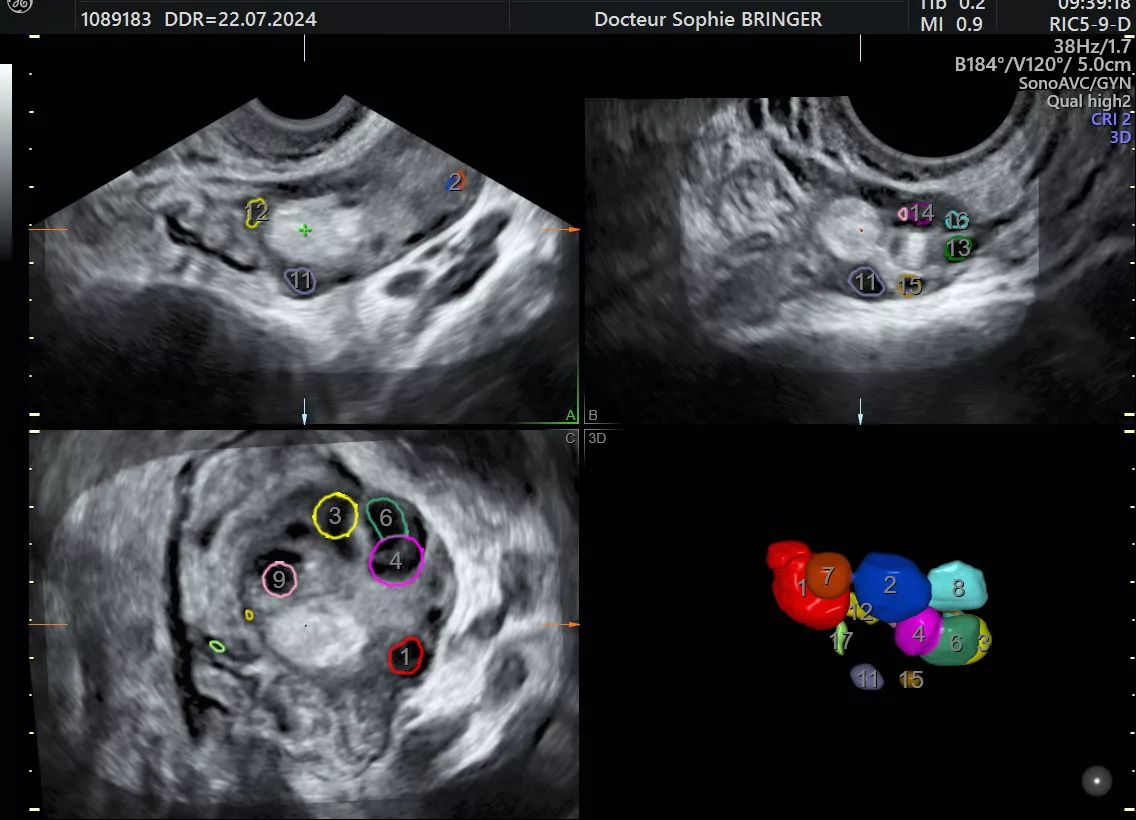

L’Échographie par voie endo-vaginale

Nécessite votre consentement explicite et absolu avant de pouvoir être pratiqué.

L’examen ne doit pas être douloureux.

Sera réalisé dans le respect de l’intégrité physique et morale de la patiente.

Signaler au praticien tous facteurs ou toutes raisons pouvant rendre l’examen désagréable.

L’examen pourra être interrompu à votre demande et sans que vous n’ayez besoin de vous justifier à n’importe quel moment.

Si vous n’avez jamais eu de rapport sexuel, l’examen sera réalisé par voie abdominale.